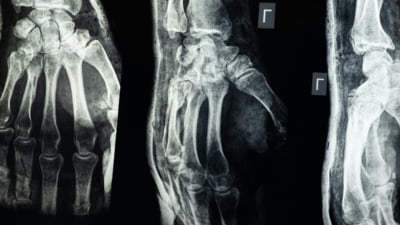

Cercetătorii chinezi susțin că au dezvoltat un adeziv osos care poate fi folosit pentru a trata fracturile și fragmentele osoase zdrobite, printr-o procedură care durează doar trei minute.

Echipa de cercetare din provincia Zhejiang, sub conducerea medicului ortoped dr. Lin Xianfeng, de la spitalul Sir Run Run Shaw, din China, a anunțat că a dezvoltat un adeziv medical inovator care ar putea schimba radical modul în care sunt tratate fracturile, potrivit Global Times.

Substanța, denumită „Bone-02", promite să repare fragmentele de os în doar câteva minute, reducând necesitatea intervențiilor chirurgicale invazive și a implanturilor metalice.

Inspirat de modul în care stridiile aderă ferm la suprafețe sub apă, echipa a încercat să reproducă acest mecanism pentru a fixa oasele fracturate. Potrivit dr. Xianfeng, adezivul reușește o fixare precisă în două-trei minute, chiar și într-un mediu bogat în sânge, situație întâlnită în timpul intervențiilor chirurgicale.

Un avantaj important al noului adeziv ar fi faptul că se absoarbe natural în organism pe măsură ce osul se vindecă, eliminând astfel nevoia unei a doua operații pentru îndepărtarea implanturilor.

În testele de laborator și în primele încercări clinice, substanța a demonstrat atât siguranță, cât și eficacitate, potrivit echipei. Într-un studiu, procedura a fost finalizată în mai puțin de trei minute, comparativ cu tratamentele convenționale care implică incizii mari și fixare cu plăci și șuruburi metalice.

Formula combină compuși de calciu și proteine specifice care asigură o legătură puternică, flexibilă și sigură. Aplicarea sa necesită doar o incizie minimă, prin care adezivul este introdus direct în zona fracturată, sigilând fragmentele osoase în câteva minute.

Până în prezent, „Bone-02" a fost testat cu succes la peste 150 de pacienți, potrivit presei chineze. Forța de lipire a oaselor a depășit 180 de kilograme, iar parametrii mecanici (rezistența la forfecare și la compresie) sugerează că adezivul ar putea înlocui, în viitor, implanturile metalice tradiționale. În plus, cercetătorii susțin că metoda ar putea reduce riscurile de reacții adverse și infecții post-operatorii.

Pe piață există deja mai multe tipuri de cimenturi osoase sau materiale de umplere pentru defecte osoase, însă acestea nu au proprietăți adezive reale. Primele încercări de a crea substanțe adezive pentru oase datează din anii 1940, dar formulele bazate pe gelatină, rășini epoxidice și acrilați au fost abandonate din cauza problemelor de compatibilitate biologică.

Rezultatele actuale, publicate de echipa din Zhejiang, indică faptul că „Bone-02" ar putea reprezenta un pas important spre un tratament mai rapid și mai sigur al fracturilor.